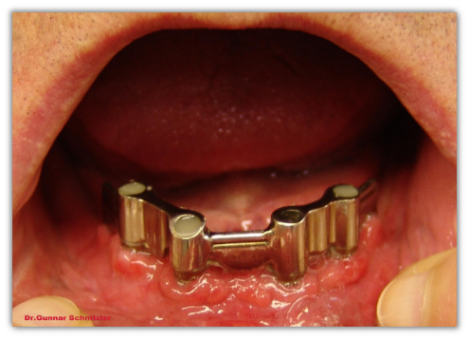

In den unbezahnten Kiefer wurden 4 Implantate ( = künstlichen Zahnwurzeln )eingesetzt. Auf diese Implantaten wurde ein Steg angefertigt, auf dem dann die Prothese sitzt.